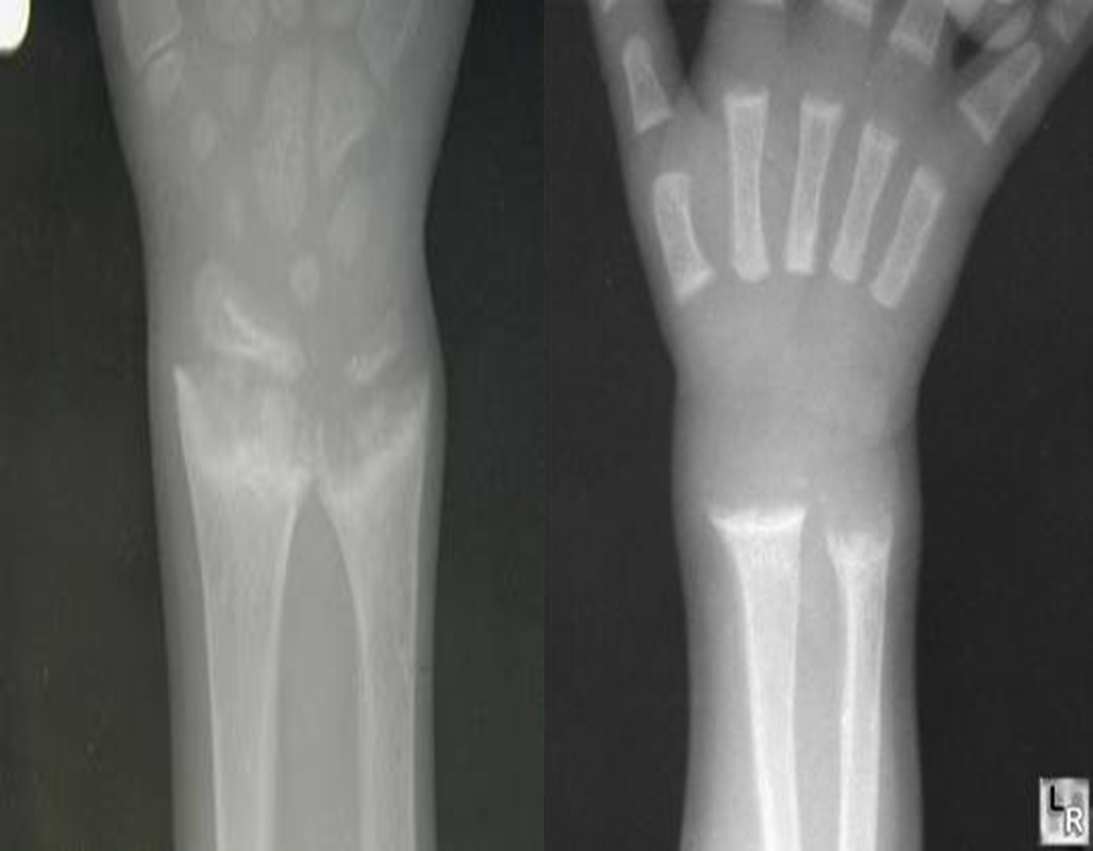

- Looser’s Zones (pseudo fractures). z

Looser’s zones Z are short lucent bands running through the cortex at right angles, usually going only part way across the bone